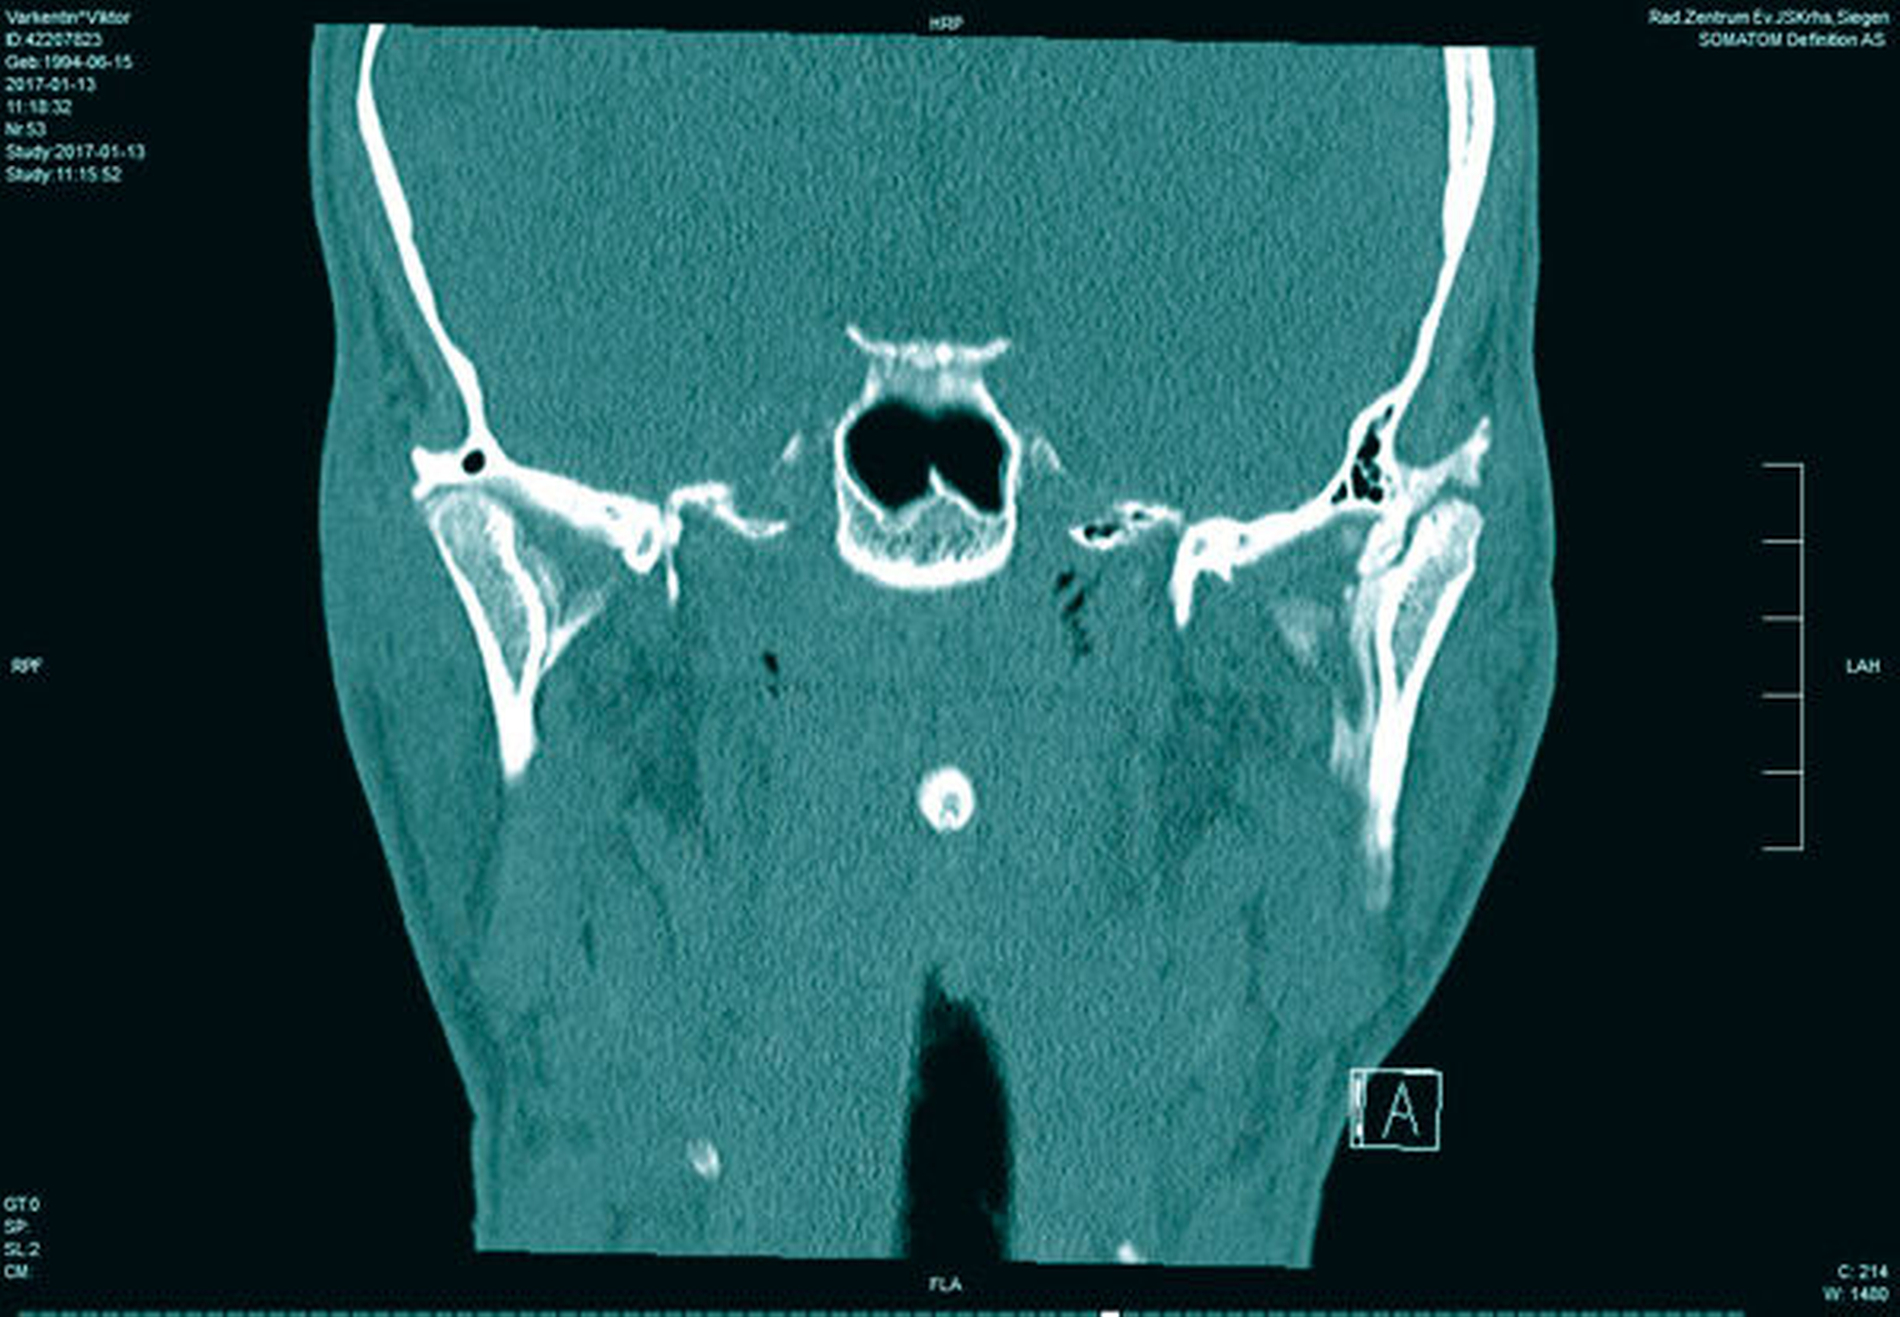

In der Folge entwickelte sich binnen fünf Monaten eine absolute Mundöffnungsbehinderung. Die SKD betrug null Millimeter. Passend zur klinischen Symptomatik zeigten sich radiologisch die Zeichen einer knöchernen Ankylose der Kiefergelenke beidseits Typ III nach Sawhney [1986] (Abbildung 1a bis 1d).